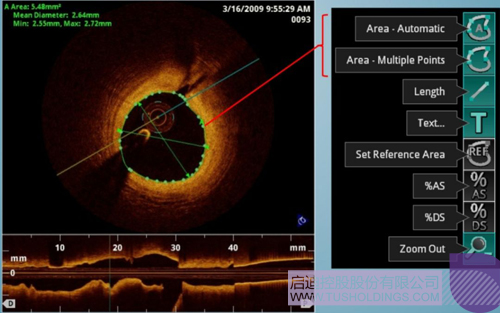

光学相干断层成像技术(OCT)是一种新型影像技术,它利用弱相干光干涉仪的基本原理,检测生物组织不同深度层面对入射弱相干光的背向反射或几次散射信号,通过扫描,可得到生物组织二维或三维结构图像。OCT由于具有极高的分辨率(10 um),可以对内膜性质和支架结构更加精确地辨别和分析。

在冠脉介入治疗迅猛发展的今天,随着复杂病变患者日益增多,血管内影像扮演了越来越重要的角色。OCT借助其高分辨率的图像优势,可以提供更清晰的病变特征和支架植入情况,OCT存在以下优势:可更精确的检测介入治疗后的血管内情况,如夹层、支架贴壁不良、组织脱垂等,另外,它在管腔直径和面积方面的测量精度更高。

血管腔内精准评估

中科微光采用的是SS-OCT技术,该技术在临床上具备显著优势,例如回拉速度更快、采样帧数更多、安全性更高。同时该技术也是当前OCT领域的最前沿技术,中科微光将争取实现国内首台内窥OCT造影系统商业化,帮助医生在手术中根据影像快速制定手术策略,帮助患者有效减少急性心梗造成的死亡等。